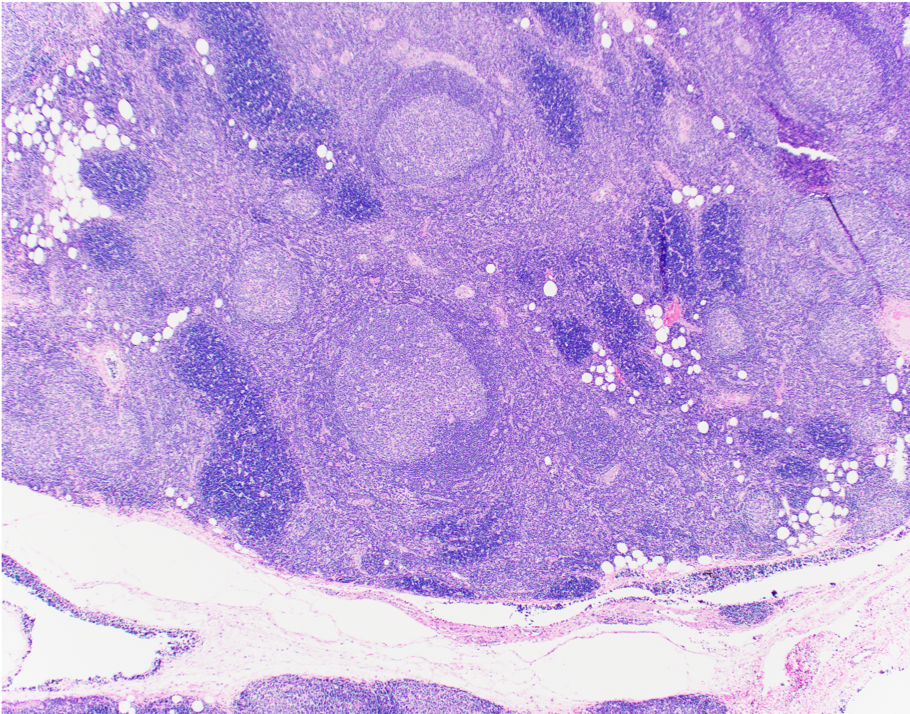

Microscopic (histologic) description

- Preserved thymic architecture

- Increased number of lymphoid follicles with prominent germinal centers of different sizes and tingible body macrophages (StatPearls: Thymic Hyperplasia [Accessed 28 February 2023], Histopathology 2009;54:69)

- Frequent Hassall corpuscles

- Rare germinal centers may be seen in the normal thymus, no clear cutoff is defined

Microscopic (histologic) images